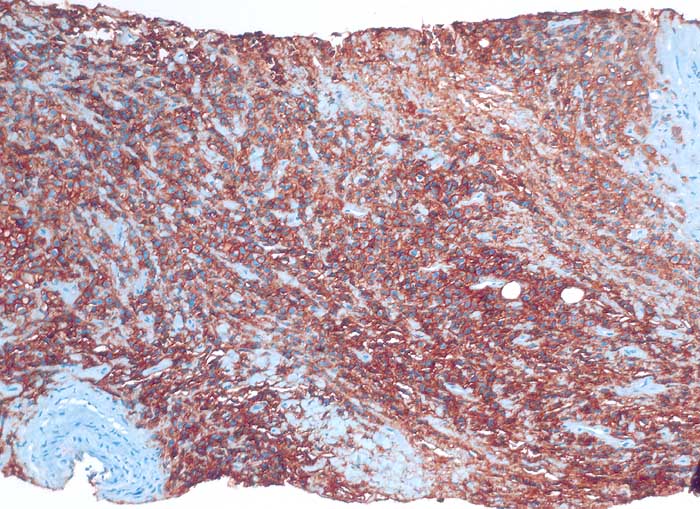

diffuses grosszelliges B-Zelllymphom

Nierenbecken

Nierenhilusweichteile: die Tumorzellen reagieren membranär positiv mit dem B-Zell Marker CD20.

Nieren-Tumor rechts. DD: Urothel-Ca.

Histologie

Immunhistochemie

CD20 (L26)

100